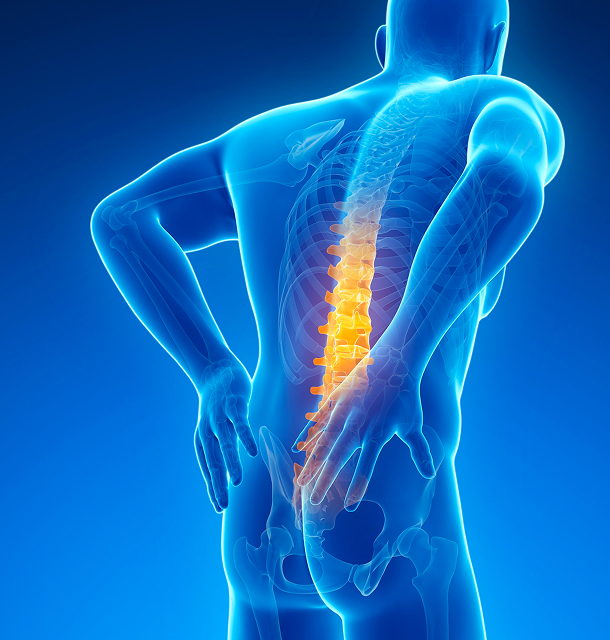

허리디스크

디스크 탈출로 인한 요통과 하지 방사통을 동반하는 질환

Lumbar Disc Herniation

허리디스크란?

허리는 우리 몸의 기둥과 중심 역할을 하는 뼈로, 각 척추뼈 사이에는 추간판(디스크)이라고 불리는 물풍선 같은 조직이 있어 각 척추 뼈가 서로 닿거나 상처입지 않도록 해주는 완충 역할과 충격을 흡수하고 분산시키는 역할을 하고 있습니다.

추간판이 퇴행성 변화나 약한 허리근력으로 인해 강한 충격을 완충하지 못하게되면, 신경 눌림 증상이 심해 저림 증상등이 발생될 수 있습니다.

허리디스크 원인

- 1허리에 무리가 가는 반복적인 행동을 하는 경우

- 2한쪽 팔, 다리를 무리하게 사용하는 경우

- 3교통사고, 스포츠 활동 중 부상 등 외부충격을 받는 경우

- 4장시간 잘못된 자세가 습관이 된 경우

허리디스크 증상

앉아있을 때, 허리를 움직일 때 심한 허리 통증

기침이나 재채기를 할 때 심한 허리통증 발생

엉치부터 허벅지, 종아리까지 통증 및 저린 증상

반대쪽 다리와 감각이 다르게 느껴지는 감각이상 발생

심한 경우 근력약화 등으로 절룩거림 및 마비증상